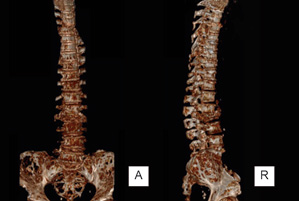

Paciente de sexo femenino de 62 años de edad, mexicana, que se presenta al servicio de urgencias por alteración del estado de alerta, desorientación, somnolencia, a su ingreso con fiebre de hasta 40 °C, TA 90/mm/Hg, FC 120x’, FR 20x’, alucinaciones visuales y lenguaje incoherente, rigidez de nuca y signos de Brudzinski y Kernig positivos, con disminución simétrica de la fuerza en las cuatro extremidades 3/5, sin focalización, al examen de fondo de ojo no se identificó papiledema. Su historia médica previa incluye historia de histerectomía por miomatosis uterina de grandes elementos, refirió lumbalgia desde 2 semanas previas, sin limitación funcional y sin haber recibido tratamiento, no ingesta de medicamentos, drogas o herbolaria y sin otros patológicos relevantes. Se identificó leucocitosis por neutrofilia, se obtiene líquido cefalorraquídeo (LCR) y se identifica turbio, con hipoglucorraquia de 13 mg/dl (rango 40-70), hiperproteinorraquia de 3200 mg/dl (rango 20-45), pleocitosis de predominio polimorfonuclear 85 % y presencia de cocos Gram positivos. Se hace el diagnóstico de meningitis bacteriana y se inicia tratamiento con ceftriaxona, vancomicina y ampicilina, no desarrolló crecimiento bacteriano en cultivo. La paciente presentó resolución de los signos meníngeos, sin embargo, al volver a estado consciente aqueja de lumbalgia intensa, dolor en miembros pélvicos y paraplejía. Se identifica en radiografía simple y tomografía la presencia de fractura por compresión a nivel de T12 y L3 y lesiones líticas en cuerpos vertebrales dorsales y lumbares, cráneo, húmeros, sacro y pelvis (figuras 1 a 3) fue valorada por neurocirugía considerándose no candidata a descompresión quirúrgica.